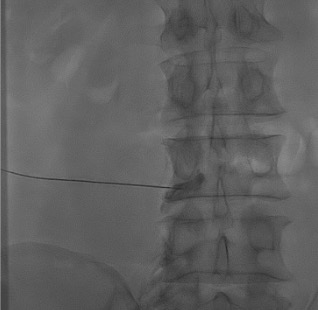

Identify interlaminar space: AP fluoroscopy; choose L4–L5 or L5–S1 interspace typically. Align spinous process midline.

Needle advancement: 22 G Tuohy or 22 G spinal needle, paramedian approach (avoids interspinous ligament; reduces dural puncture risk). Advance incrementally under intermittent fluoroscopy.

Interlaminar needle placement under fluoroscopy — paramedian approach through the ligamentum flavum at L4–L5 or L5–S1 interspace.Contrast test showing the characteristic epidural spread pattern — tracking bilaterally around the dural sac and along exiting nerve root sleeves. Confirms correct placement prior to steroid injection.